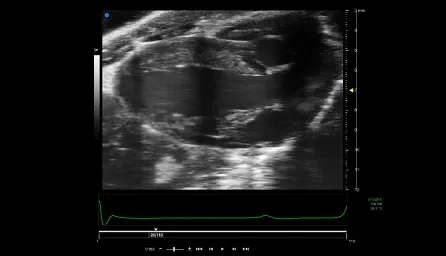

Figure 1: High resolution image of left ventricle on adult mouse heart

• Measurement of cardiac function in 2D, 3D and 4D (Figure 1)